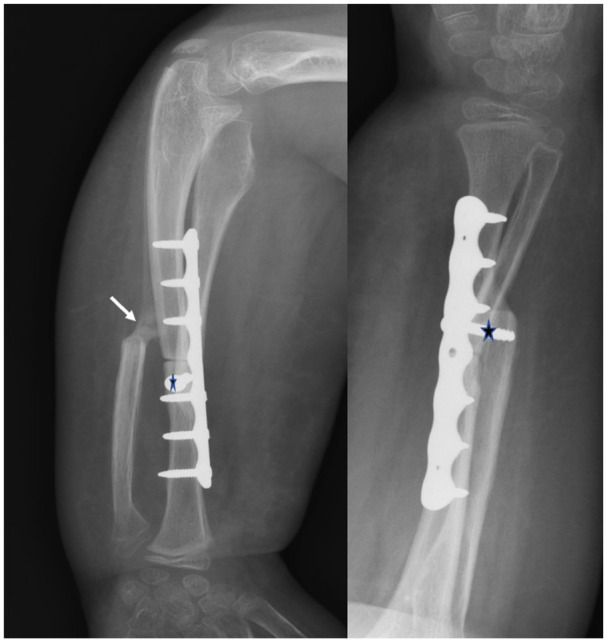

Background: The one-bone forearm procedure has been considered as a potential treatment for severe forearm deformities. However, its primary limitation lies in the elevated risks of nonunion and infection. In order to enhance union rates, a technical modification was introduced, aiming not only to establish end-to-end radio-ulnar fixation but also to incorporate an additional overlay and fixation between the proximal and distal radius osteotomy stumps. This technique, initially applied in a heterogeneous patient population including individuals with neurological, tumoral, and congenital conditions, yielded promising results, achieving a consolidation rate of 100% and enabling supination corrections of up to 120°.

Methods: In this study, we present a retrospective cohort of 28 patients, with an average age of 9 years, all afflicted by forearm supination contracture exceeding 90° secondary to neonatal brachial plexus injury. These patients underwent treatment with the modified technique.

Results: The mean correction achieved in forearm rotation was 116°, and the average follow-up period extended to 43 months. Remarkably, all patients exhibited bone union within an average period of 6.6 weeks, without any complications.